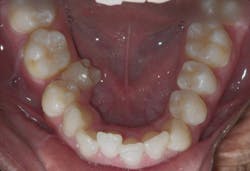

Case 3: 17-year-old male: 1-year treatment. Expanding and proclining delivered more room for the tongue and increased oral cavity volume without IPR or extractions. Case and photos courtesy of Dr. Ben Miraglia.

Before: V- and omega-shaped arch, crossbite. After: U-shaped arch, no IPR, no EXT, increased oral cavity volume.